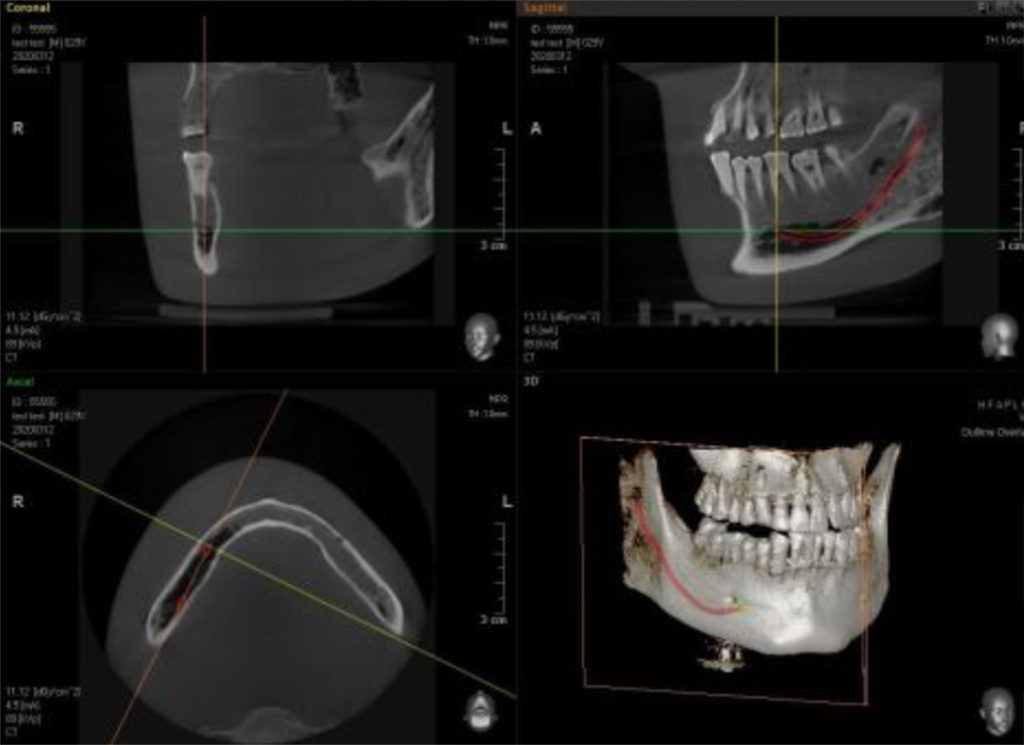

3D電腦斷層掃描

十多年前在植牙治療尚不普及時,欣鴻牙醫診所已率先採用當時最新科技3D導航電腦斷層,讓每位患者在手術前從口腔至鼻竇內皆可精準定位。今年,更汰舊換新購置全3D醫學中心級專業設備RAYSCAN ALPHA PLUS,影像可大範圍覆蓋全頭顱,為植牙帶來更高的精確度﹗

精準呈現 細節一覽無遺

數位化3D電腦斷層掃描,突破了傳統2D掃描的限制,立體呈現讓視覺毫無死角,連困難的All on 4植牙所需角度皆一次收錄,視覺化完整顯示神經區域及骨骼深度、硬度,讓植牙醫師更準確的進行植牙,不放過任何細微的病灶,幫助醫師縮短手術時間,傷口小、復原快速、治療品質大幅提升。

3D數位Face Scan 效果看得見